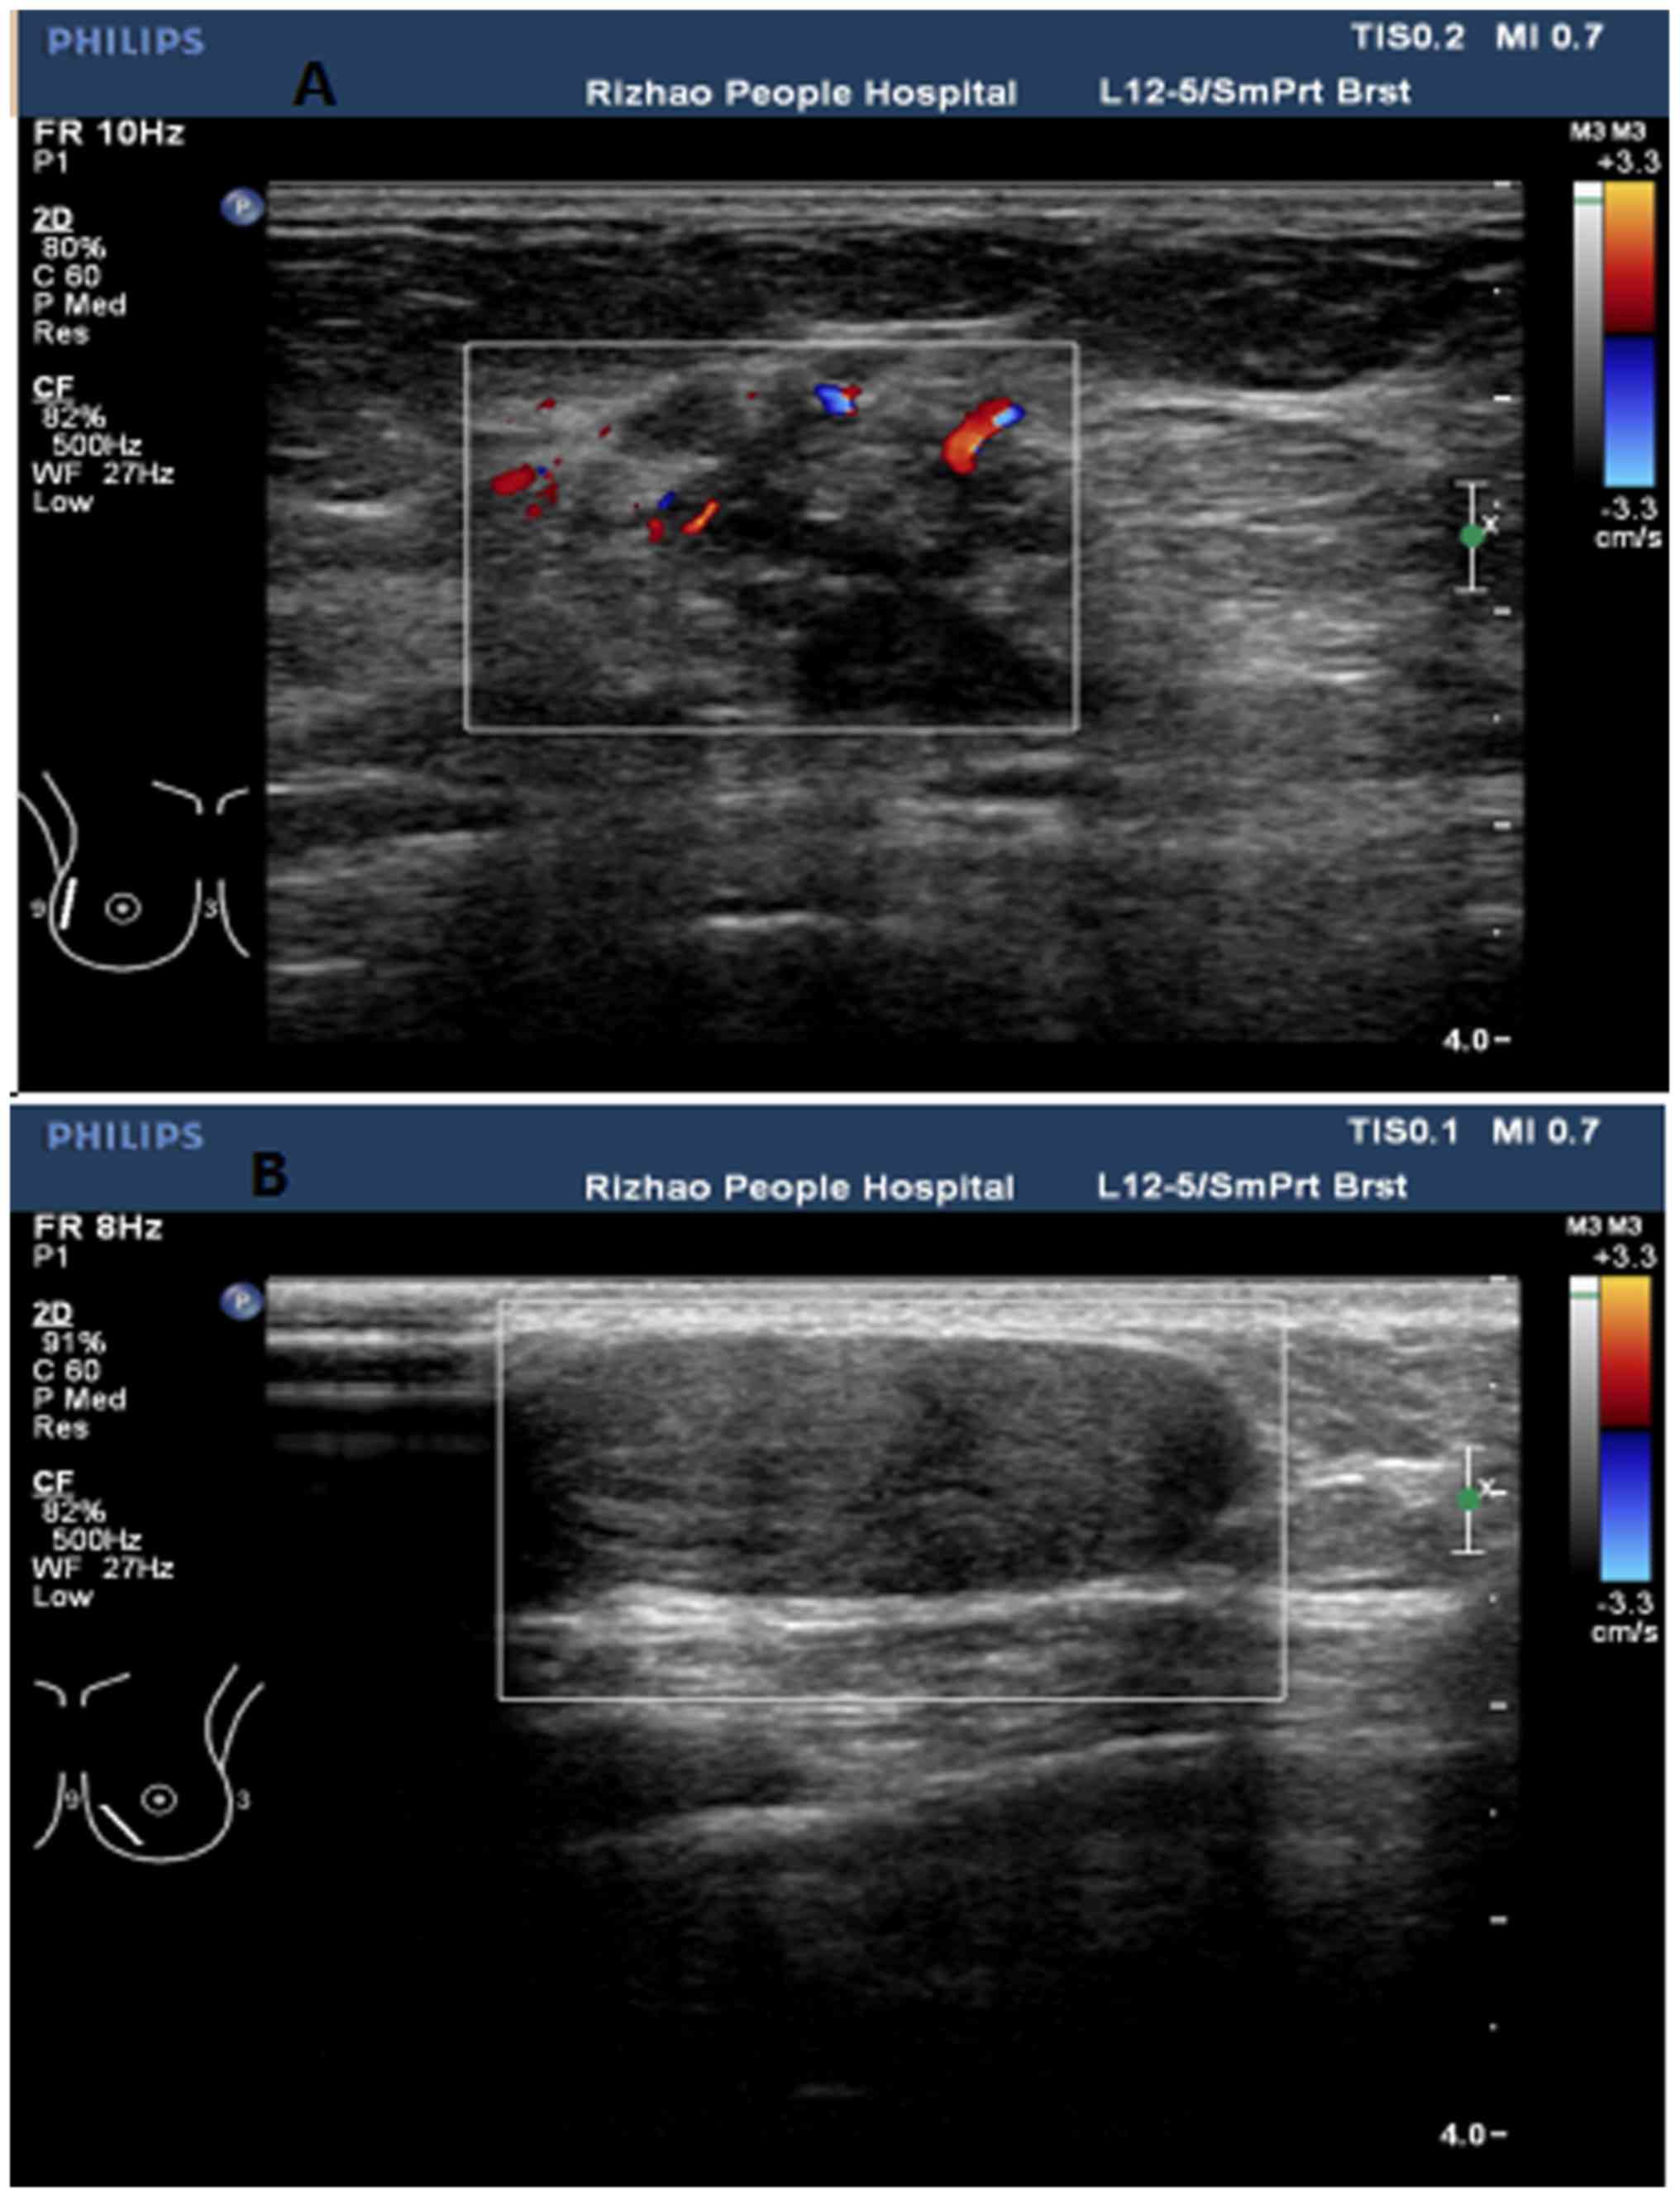

Ultrasound imaging allows better evaluation of the status of the axillary lymph nodes in patients with ibc, an important step in determining extent of disease prior to initiation of chemotherapy. However, a dark spot on your ultrasound doesn't mean that you. It is the most common cause of cancer death in women. in 2005 alone, 519 000 deaths were recorded due to breast cancer. this means that one in every 100 deaths worldwide and almost one in every 15 cancer deaths were due to breast cancer. On ultrasound, a breast cancer tumor is often seen as hypoechoic, has irregular borders, and may appear spiculated. In the table the differences in ultrasound appearances are listed.

Cysts, tumors, and growths will appear as dark areas on the scan. Breast ultrasound uses sound waves to make a computer picture of the inside of the breast. What does a solid mass look like in an ultrasound breast image? Ultrasound of triple negative breast cancer. This is a network of thin tubes (vessels) and nodes that carry a clear fluid called lymph around the body. A breast ultrasound is most often done to find out if a problem found by a mammogram or physical exam of the breast may be a cyst filled with fluid or a solid tumor. Solid lesions can be a little brighter or darker than the surrounding tissue, and the way to evaluate these on ultrasound is to look closely at the margins or the outer edges of the nodule. In the table the differences in ultrasound appearances are listed. Ibc is a rapidly progressive, aggressive form of breast cancer associated with a low overall survival rate. On the flip side, there are benign (not cancerous) breast changes which can mimic breast cancer as well. What does breast cancer look like on a mammogram? American cancer society, 9 oct 2017. Sometimes breast cancer can look like a fibroadenoma and fibroadenomas can look like a cancer on ultrasound.

This breast cancer ultrasound image shows changes related to breast cancer that are not seen as microcalcifications or a mass or lump. Any area that does not look like normal tissue is a possible cause for concern. If your breast tissue is too dense for a mammogram. Ultrasound imaging allows better evaluation of the status of the axillary lymph nodes in patients with ibc, an important step in determining extent of disease prior to initiation of chemotherapy. If a solid lump shows on the scan you might need to have. It is the most common cause of cancer death in women. in 2005 alone, 519 000 deaths were recorded due to breast cancer. this means that one in every 100 deaths worldwide and almost one in every 15 cancer deaths were due to breast cancer. With ultrasound, the radiologist will probably be trying to get a sense of the internal texture of the breast lesion and surrounding area. Physical examination and mammogram can be more accurate in some settings. If there are calcifications within the nodular dcis, one may be able to see these on ultrasound as white flecks. The images that a breast ultrasound produces are in black and white. A diagnostic mammogram is used to check for breast cancer when there is a sign or symptom of disease. A breast ultrasound is most often done to find out if a problem found by a mammogram or physical exam of the breast may be a cyst filled with fluid or a solid tumor. To look more closely at a.

Any area that does not look like normal tissue is a possible cause for concern. Below are images of dcis on breast ultrasound. Ultrasound is not used on its own as a screening test for breast cancer. Ultrasound (us) shows an irregular, hypoechoic (dark gray) spiculated mass (arrow), highly suspicious for cancer. This is because it may miss some early signs of cancer.

Staging Of Breast Cancer With Ultrasound Sciencedirect from ars.els-cdn.com Ultrasound characterization of breast masses. indian journal of radiology and imaging. Other names for this test: Ultrasound is only one means of evaluation of the breast. Tumors are likely to be smaller when doctors detect them early, which can. Breast cancer is among the most common causes of cancer deaths today, coming fifth after lung, stomach, liver and colon cancers. Any area that does not look like normal tissue is a possible cause for concern. In the table the differences in ultrasound appearances are listed. Overall, 57 (20.8%) of the 274 women had cancer in the axillary lymph nodes.